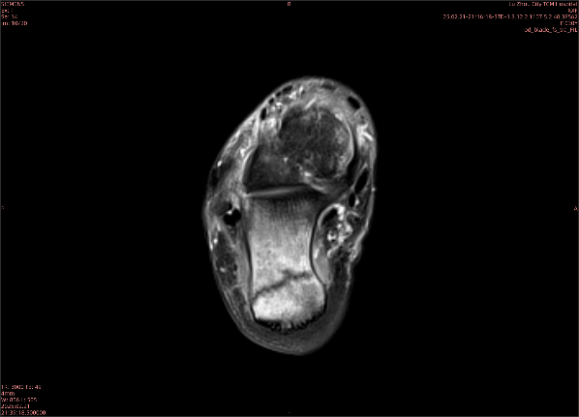

隱性骨折在MRI表現(xiàn)為T1WI序列上見由關(guān)節(jié)面向骨干走行的形態(tài)各異低信號(hào)區(qū),有線狀、條狀、紊亂低信號(hào),信號(hào)強(qiáng)度不均勻。與T1WI低信號(hào)改變相對(duì)應(yīng)部位在T2WI上表現(xiàn)為相應(yīng)形狀的高、低混雜信號(hào),且部分低信號(hào)周圍可見高信號(hào)水腫改變。STIR序列圖像上病灶呈顯著高信號(hào),與信號(hào)被抑制的臨近正常骨髓形成鮮明對(duì)比,分界也較T2WI成像更為清楚。脂肪組織抑制技術(shù)是MRI的一個(gè)重要性能,脂肪抑制技術(shù)在MRI應(yīng)用中可以改善組織對(duì)比和增加病變顯示機(jī)會(huì),這樣骨髓的脂肪抑制后就不會(huì)有任何信號(hào),而隱性骨折線及骨髓水腫的異常高信號(hào)就會(huì)更加明顯的顯示出來。

舉例圖像

圖2

專業(yè)解釋看不懂沒關(guān)系,大家看圖1和圖2就可以了,這是同一個(gè)患者跟骨的磁共振和CT圖像,圖1的紅色箭頭指示的黑線就是磁共振圖像顯示的骨折線,一目了然。而對(duì)比圖2的CT圖像上并未顯示異常。